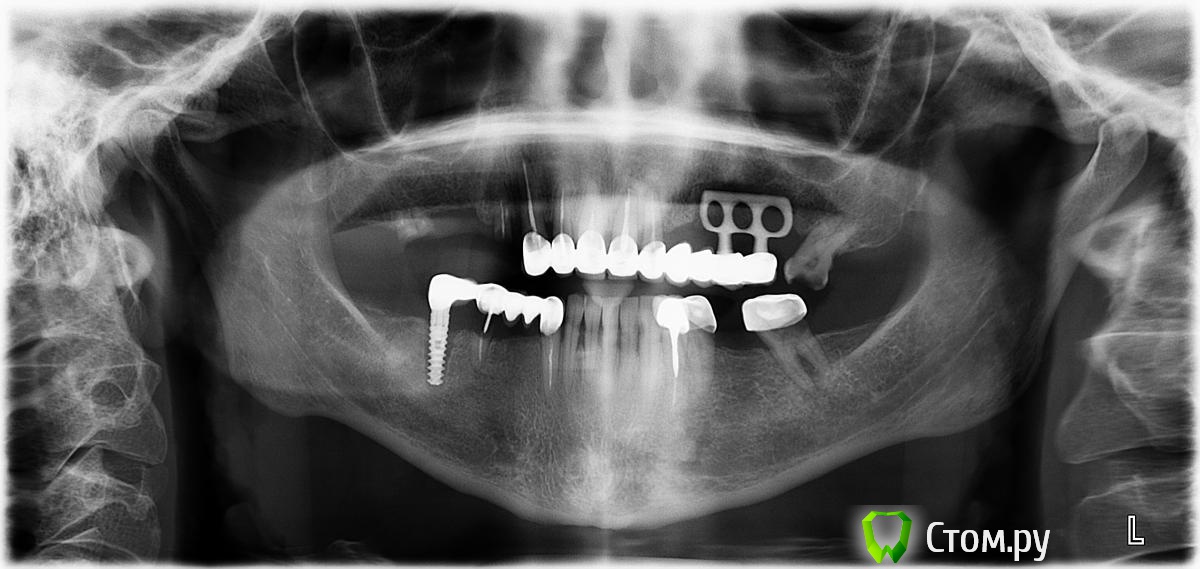

TIGER Опубликовано 3 сентября, 2014 Поделиться Опубликовано 3 сентября, 2014 Повесьте jpg пожалуйста!Здесь тоже всё стоит лет 20.....это хорошо? Ссылка на комментарий

faity Опубликовано 3 сентября, 2014 Поделиться Опубликовано 3 сентября, 2014 Повесьте jpg пожалуйста!Здесь тоже всё стоит лет 20.....это хорошо? до определенного момента... Ссылка на комментарий

TIGER Опубликовано 4 сентября, 2014 Поделиться Опубликовано 4 сентября, 2014 человека устраивает? к вам зачем пришёл?как может это устраивать?пришёл привести в порядок полость рта,и улучшить эстетику Ссылка на комментарий